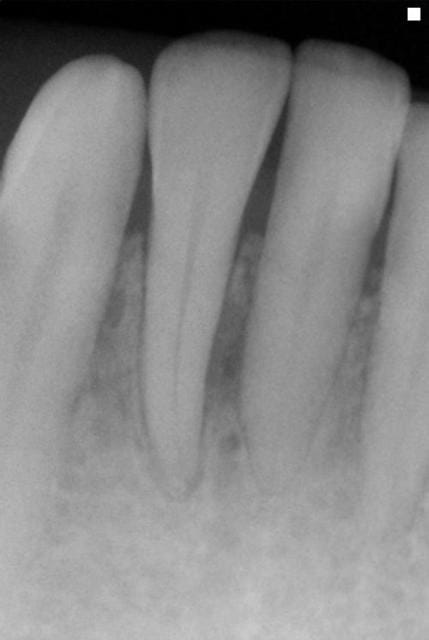

pour narik; oui , la rvg n'était sans doute pas sur le même réglage

est ce que tu as des radios intermediaires? si la radio de depart et celle d'arrivée n'ont pas la meme expo ...Comme d'autre part on ne fait pas de sondage, c'est un peu difficile d'evaluer vraiment le point de depart: quand tu dis un abcés, il y avait une fistule externe? petit oedeme en goutte sur la paroi Vest? la dent etait mobile ? ne l'est elle plus+

J'étais plus intervenu depuis longtemps parcequ'on m'avait dans les hautes sphères d'eugénol,demandé de me calmer,mais je peux pas laisser passer ça.On est dans un cas typique de guérison à la Sainte Carole, priez pour nous.La radio de départ elle est pourrie de chez pourrie.Comment on peut faire un diagnostic dans ces conditions?Comment on peut affirmer qu'il y a eu guérison, s'il n'y avait pas de lésion au départ.C'est absolument n'importe quoi.Il suffit de passer ces deux images à photoshop pour se rendre compte que les niveaux ne correspondent pas,et que sur la première image on est surexposé,ce qui brûle obligatoirement certaines zones de l'image,et que sur la deuxième on est sous exposé.Dans ces conditions,c'est ni six mois,ni trois,ni un jour,c'est en une seconde que je vous obtiens autant de guérisons miraculeuses que vous voulez.Y a vraiment personne qui réfléchit ici avec sa tête au lieu de s'extasier sur rien?pierres,va faire un stage de prise de radio avant de penser que tu es devenu un parodontiste émerite.

la différence d'exposition entre les deux clichés est évidente aussi, et c'est un défaut de la présentation.

Ceci dit , cela rend intéressant à postériori l'usage des réglages contrastes pour visualiser l'os à perdre ou à regagner. Le numérique nous le permet. La question étant y a t il encore une trame ou plus rien.